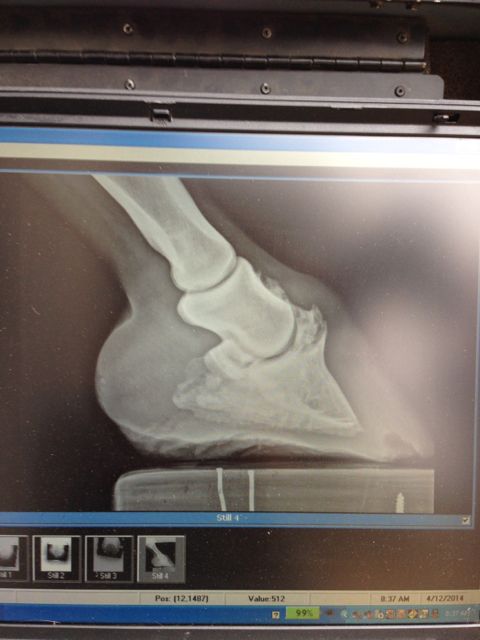

Posted on Saturday, May 3, 2014 - 2:13 am: Greetings! I just rescued a 10 year old quarter horse mare with a coffin bone injury. The first vet thought she just had a healing abscess.. wrong! I have learned my lesson to always get radiographs before committing to a horse She is really lovely though so I am hoping for some hope and good advice in terms of treatment. Right now she is on 1 -2 gm of bute a day and just walking and turn outs. In the soft arena she presents as alllllmost sound - to sound (w/t/c) on a good day. Some days she is sound at the walk even on harder ground. I am new to this forum and not sure if I am doing this right but I really appreciate any advice! Here is her Radiograph:

Posted on Saturday, May 3, 2014 - 6:46 pm: Hi Anah, Horses do have a way of teaching us lessons don't they. I'll be interested in what Dr. O says about this radiograph. Hope he chimes in soon. It looks as if there is some rotation, or at least the trim is a bit off. Notice how the front of the coffin bone bottom surface (palmar) is lower than the back by a few degrees? |

Posted on Monday, May 5, 2014 - 2:26 pm: Welcome Anah,I suspect this started as a avulsion fracture on the extensor process. It is hard to give advice without knowing what your goals are but from a soundness standpoint, it is hard to imagine that any horse with the above lesions will ever remain riding sound for any time. The osteoarthritis in the coffin joint is just too remarkable. DrO |

Posted on Sunday, May 11, 2014 - 6:36 pm: Hello Anah,You can find my overall thoughts about nerving at HorseAdvice.com » Diseases of Horses » Lameness » Diseases of the Hoof » Neurectomy and Nerving: A Farriers View. I did not write this article but support its perspective. In the case of the horse in the radiographs above I would not recommend a posterior digital neurectomy. Neurectomy is best reserved for cases when imaging indicates structures that appear healthy and functional and there are no obvious problems that will become progressive with use. I do not believe that is the case with your horse. DrO |